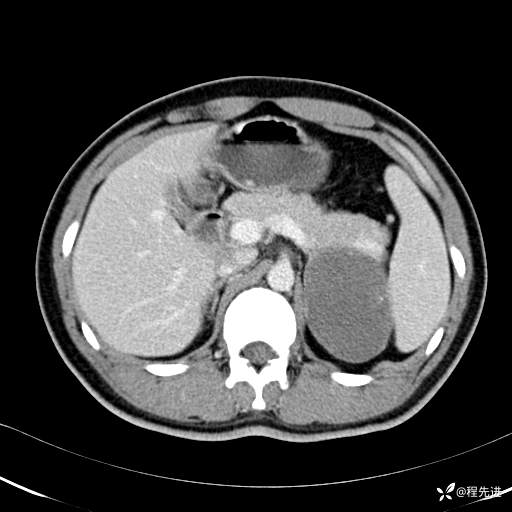

平衡期: